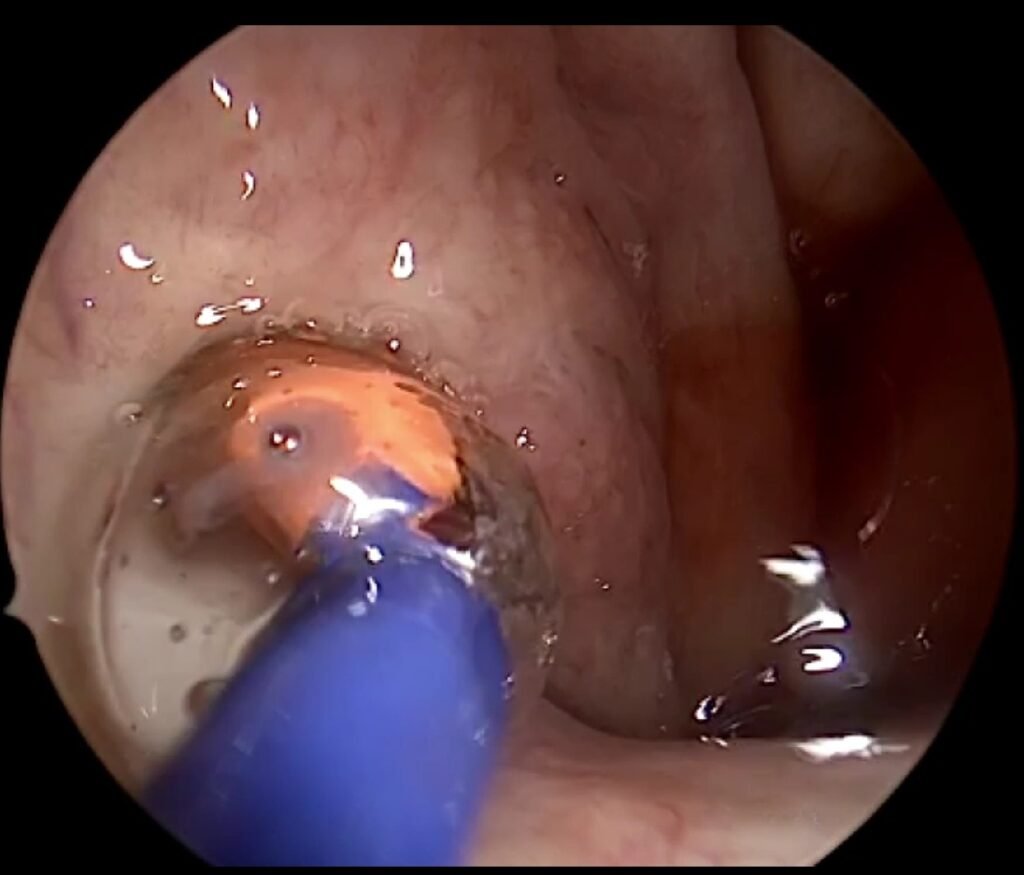

Eardrum repair in London (myringoplasty or tympanoplasty) is a surgical procedure to close a hole or tear in the tympanic membrane. A perforated eardrum may cause hearing loss, repeated ear infections, ear discharge, tinnitus, or discomfort.

The Procedure

Most eardrum repairs in London are performed as day-case procedures. Minimally invasive techniques are used wherever possible, meaning no external incisions, less discomfort, and a shorter recovery period.